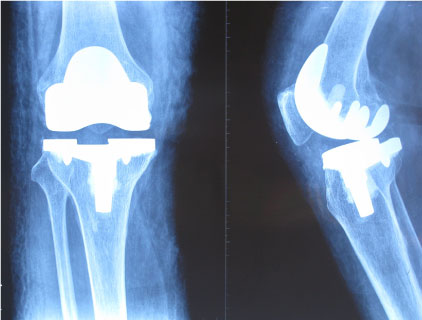

In group A, we did a thorough haemostasis by releasing the tourniquet after the cemented prosthesis fixed during the operation by using either electrocoagulation or bone wax to stop the significant bleeding from the tissue and bone. In group B, we used the tourniquet all through the operation and there were no significant bleeding at all, since the tourniquet worked through the operation. And we did not perform any haemostasis action at all. After the closure of the wound, we used elastic bandage for both group and one redivac suction drain was routinely used in all patients and removed within 24 h. (Figure 1, Figure 2 and Figure 3). Comparing the demographics, clinical and surgical details of patients in both groups (Table 1).

Figure 2: X-ray of the post-operation with a total knee arthroplasty. View Figure 2